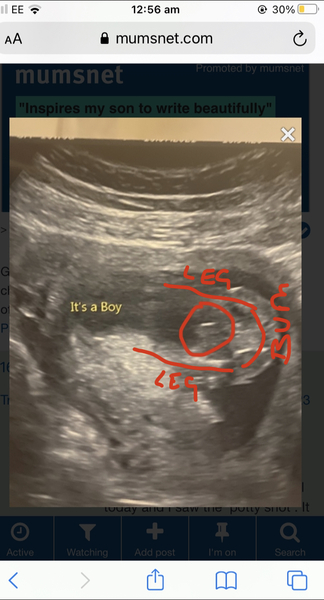

I had a 16 week scan the other day and we did the gender reveal today and I saw the ‘potty shot’. It doesn’t look like the potty shot I have seen before, and looks like it’s more of a side view. I’m just wondering what they have pointed out to be the penis has a line going down the middle and looks a lot bigger than other penis shots I’ve seen!! Is this normal? What is the line down the middle? They didn’t flag up any concerns at the scan!! Has anyone who had boy scans had something similar?